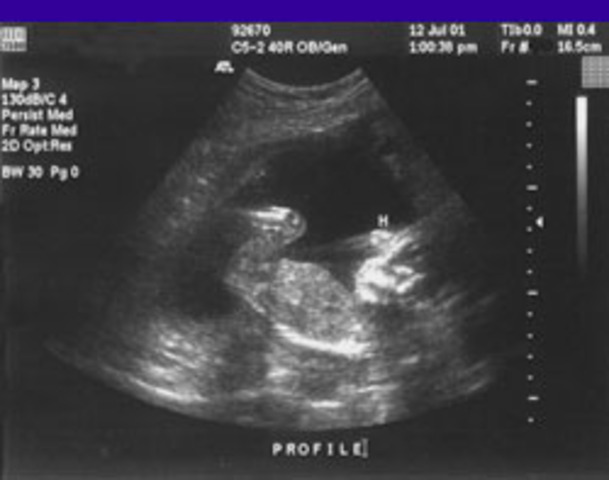

• Week 30

Kuro has gotten chubbier and his face looks alot like what it will look like when he is born. He can move his head, make breathing movements and open his eyes. If he was born today, he would have a good chance of surviving. He is 15.7 inches long and is about 3 pounds.